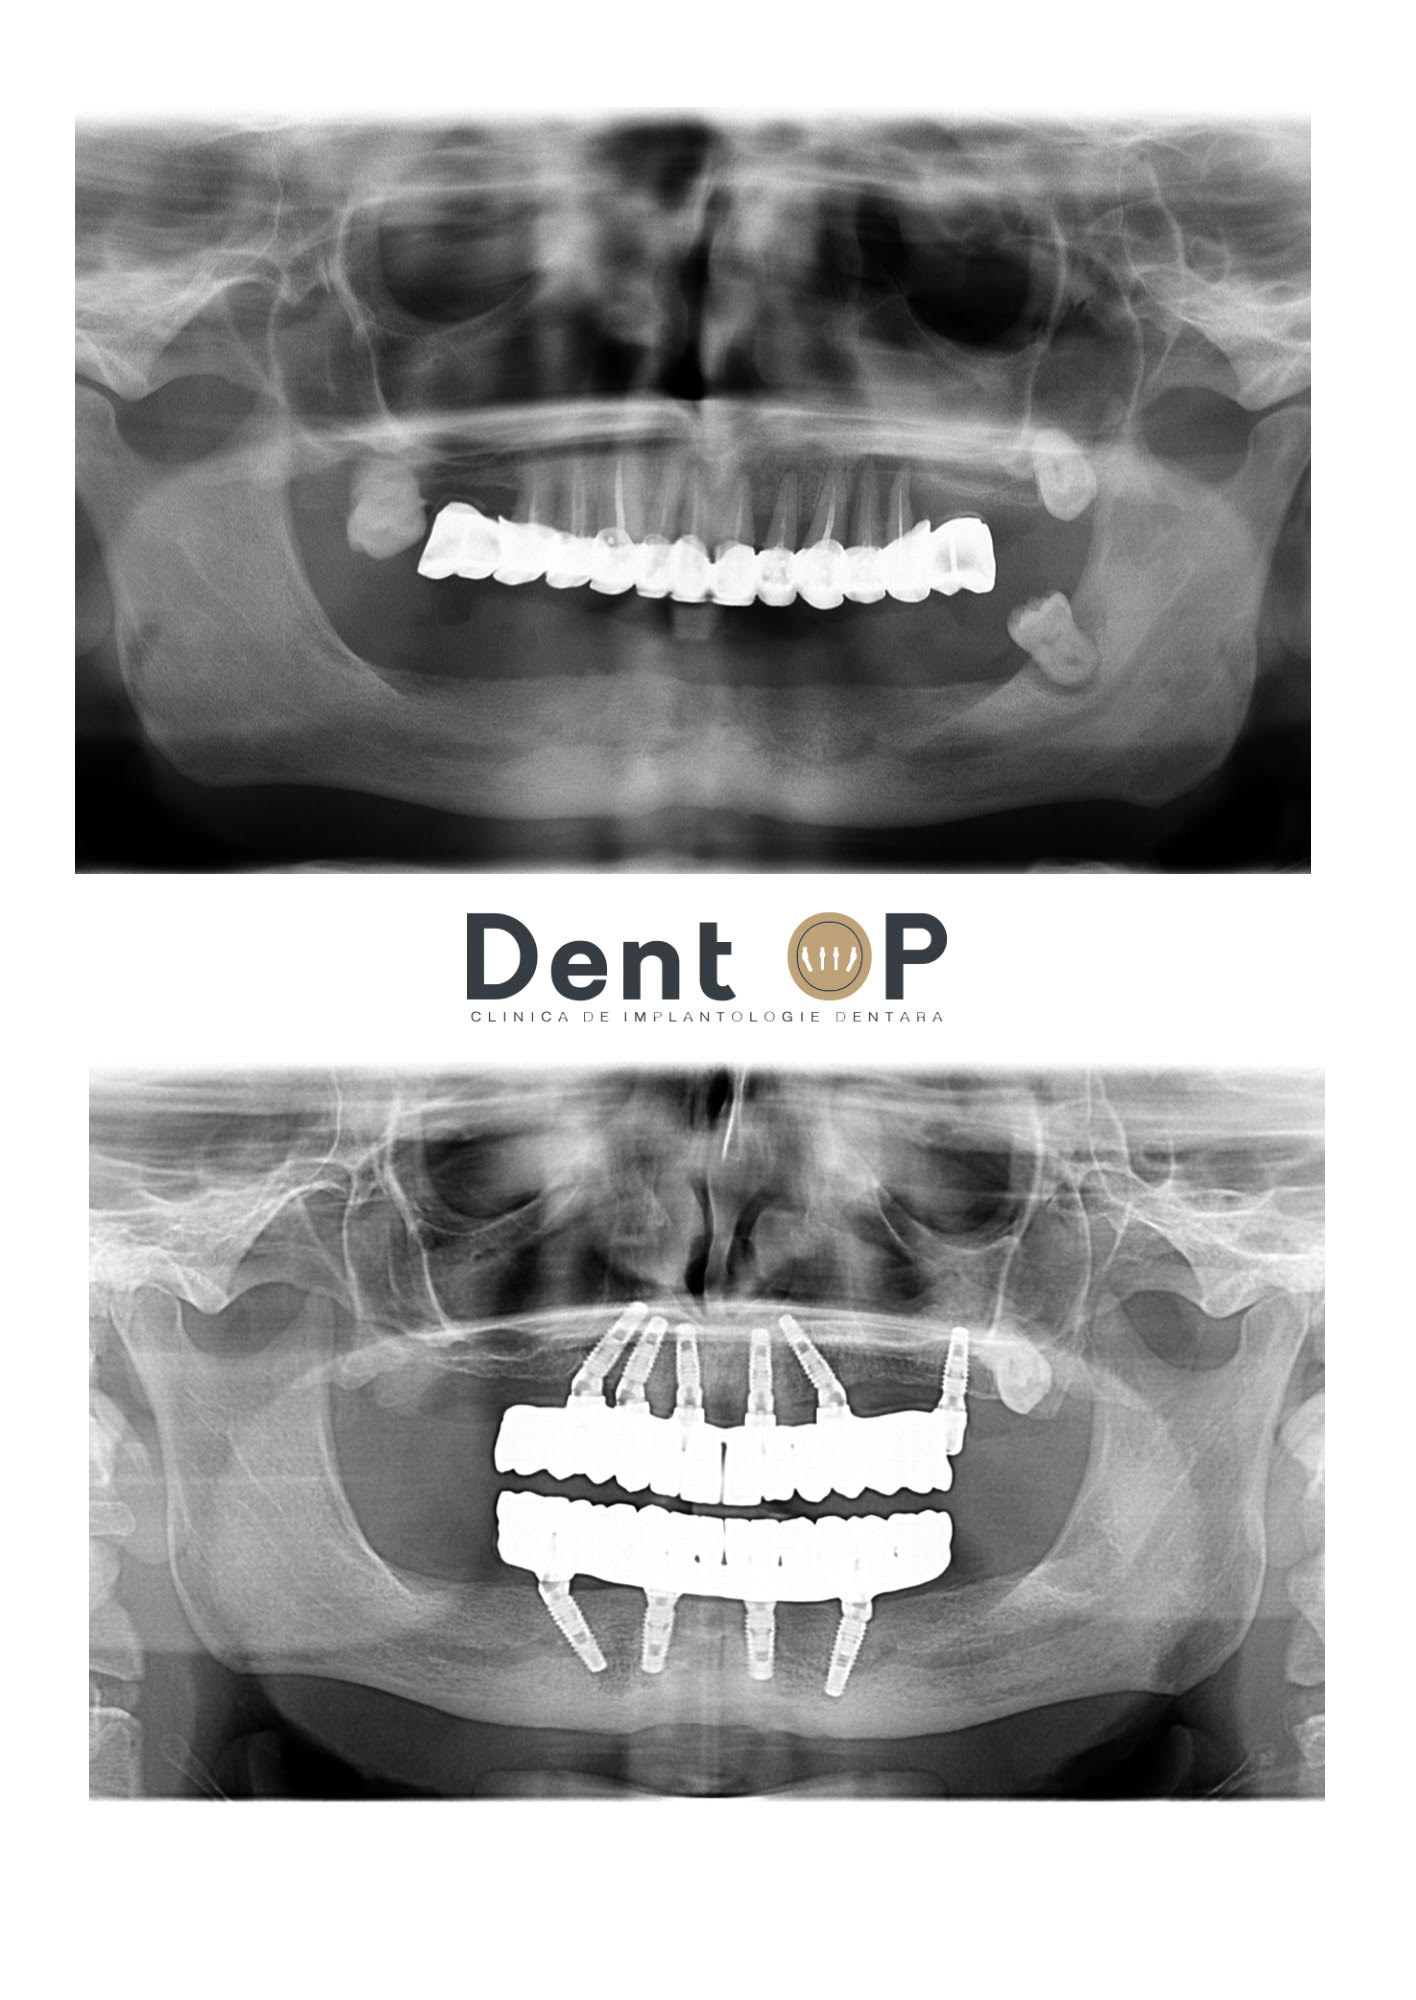

În radiografiile de mai jos putem observa cum arăta dantura domnului B. înainte și după inserarea celor 6 implanturi dentare la maxilar și 4 la mandibulă.

La maxilar, Domnul B. avea o serie de lucrări mai vechi, iar la mandibulă o placă mobilă ce a cauzat resorbție osoasă.Aceasta nu era stabilă, întrucât domnul B. nu putea mânca corespunzător. Deși în mod normal purtarea plăcii mobile la mandibulă poate părea mai simplă decât cea la maxilar din cauza forței gravitaționale, nu este așa. Purtarea plăcii mobile la mandibulă poate deveni deranjantă deoarece este constant afectată de mișcările limbii și obrajilor. Boala parodontală i-a afectat întru totul dantura, dar acum se bucură de dinți frumoși și sănătoși după experiența în cadrul clinicii DentOP.